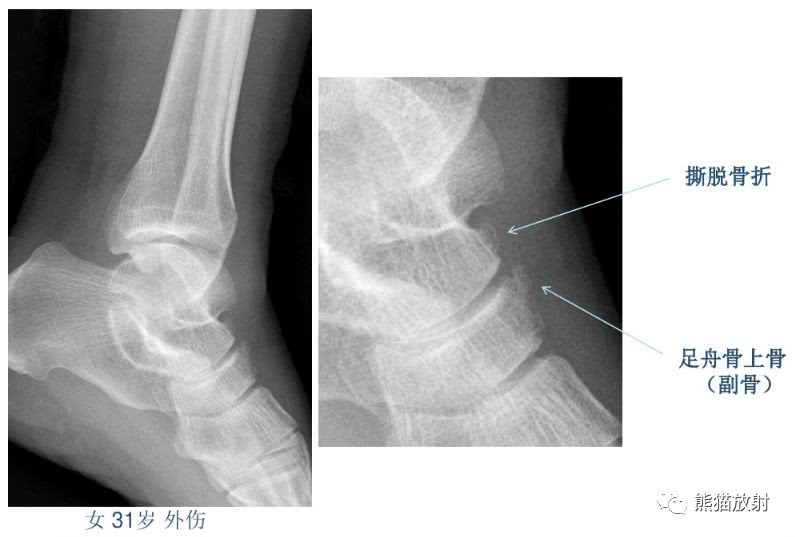

籽骨、副骨、永存骨骺、撕脱骨折?读完此文,你